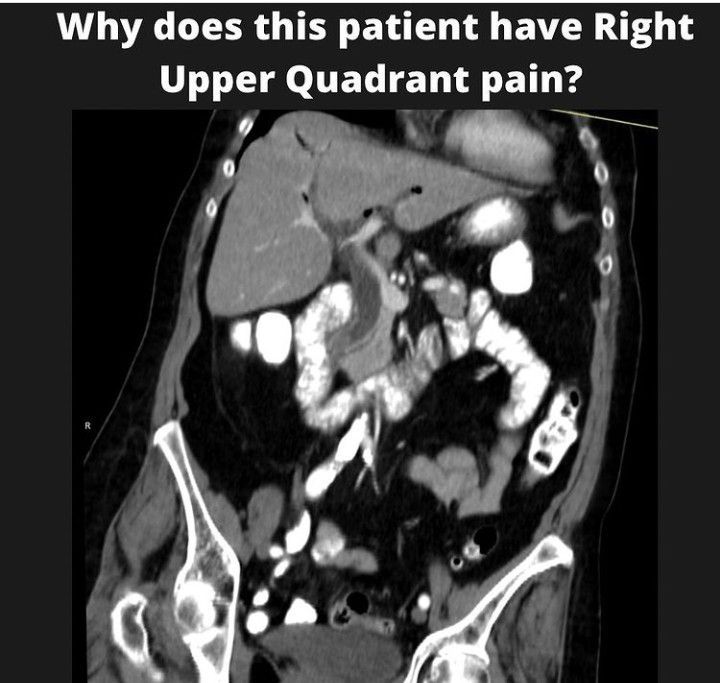

Choledocholithiasis

Choledocholithiasis is the presence of at least one gallstone in the common bile duct. The stone may be made up of bile pigments or calcium and cholesterol salts. The liver produces bile which aids in the digestion of fats.